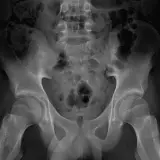

Over 2,100 interactive radiology cases, curated by radiologists for your level of training. Scroll, window, and view cases full screen — just like on PACS. Click linked findings in each writeup to jump straight to them on the image. Cases include sample reports, a focused discussion section, original illustrations, and videos.

Casos totalmente interactivos con las herramientas que esperaría de un PACS: scroll, ventana, zoom, pan, mediciones, ROI y modo de pantalla completa.

• Anotaciones enlazadas

Anotaciones extensas resaltan los hallazgos clave directamente sobre los casos. Haga clic en los hallazgos enlazados dentro de la descripción del caso para saltar a su ubicación exacta en el estudio.

Aprenda con eficiencia gracias a hallazgos de imagen anotados e ilustraciones